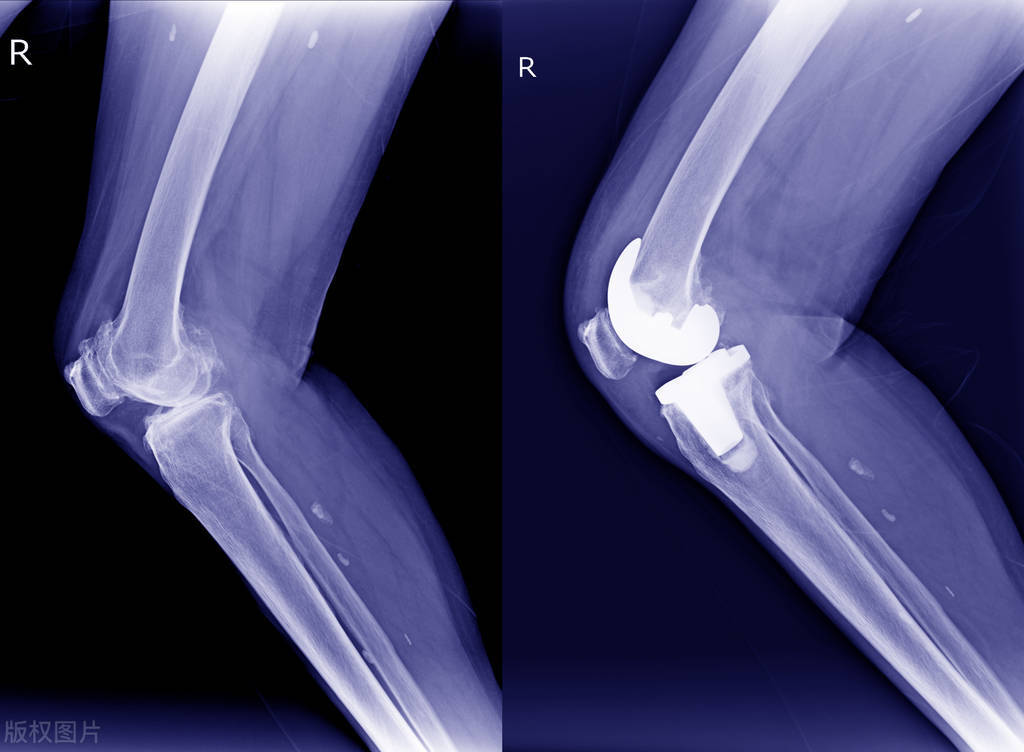

人老先老腿。随着右膝关节的病变,我不得不接受人工关节置换手术。